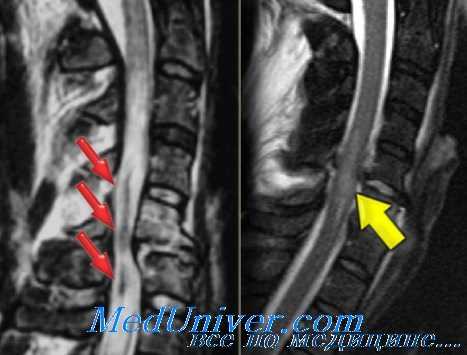

(Слева) STIR МР-И, сагиттальная проекция: флексионно-дистракционное повреждение позвоночника, признаки отека на фоне разрыва межостистой связки на уровне L2-L3. Обратите внимание на небольшой антелистез L2 позвонка и компрессию переднего отдела тела L3. Кзади от тела L2 видна небольшая эпидуральная гематома.

(Справа) STIR МР-И, сагиттальная проекция: флексионно-дистракционное повреждение позвоночника, визуализируется отек/кровоизлияние на фоне разрыва межостистой связки. ЗПС отслоена от тел ТА и Т5 позвонков, имеет место перелом Т6 с утолщением и деформацией ППС.